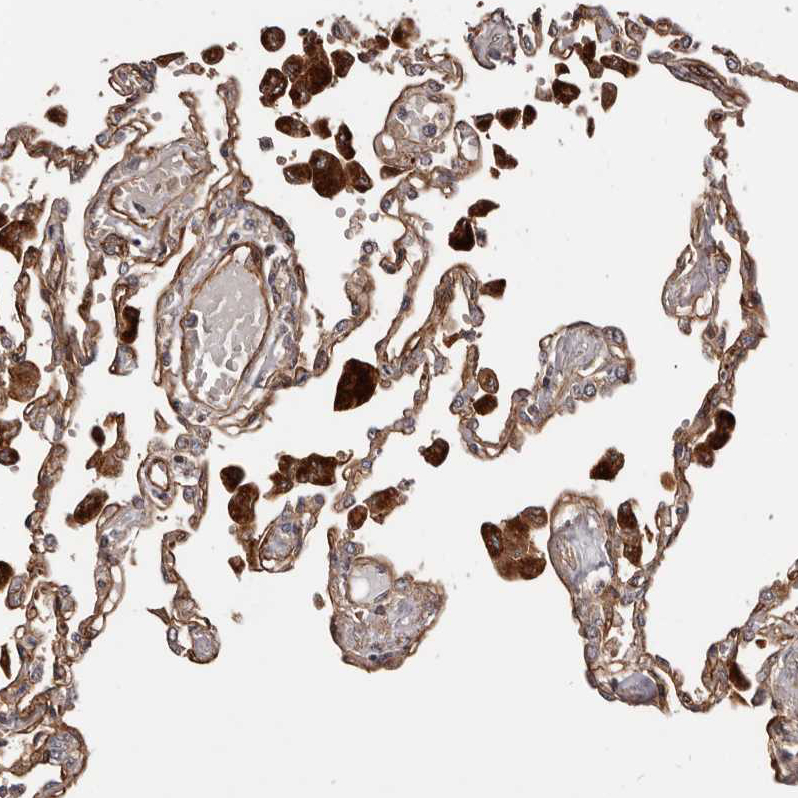

Immunohistochemical staining of human lung shows strong cytoplasmic positivity in macrophages.